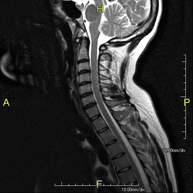

- Thoracic spine MRI

This non-invasive diagnostic procedure uses an electromagnetic field and radio waves (from a transmitter and receiver) to acquire high-definition anatomical images of the thoracic spine. It is a radiation-free procedure. Indicated for: trauma, degenerative problems, hernias, tumours.

- Cervical + thoracic spine MRI

This non-invasive diagnostic procedure uses an electromagnetic field and radio waves (from a transmitter and receiver) to acquire high-definition anatomical images of the cervical and thoracic spine. It is a radiation-free procedure. Indicated for: trauma, spinal degeneration, hernias.